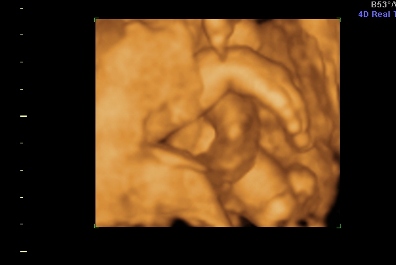

Na hát megvolt a 4D. Jó sokat időztünk ott, Mártika annyira kedves volt kaptam csokit ,colát, sétáltam mert a drágánk a feje előtt tartotta a két kezet plusz az egyik lábfejét, és belebújva a méhlepénybe. Szóval alig se nagyon látszott valami kb 1órát időztünk. HÁt ezért szeretek én a Genesisbe menni mert annyira lelkiismeretesek.

Hoztam pár képet

pofi

Kép

keze

tuti lányos